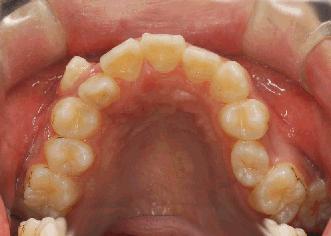

在我国,成年人的牙周炎的发病率比较高,但是病因复杂,通常需要进行全面的牙周健康综合治疗措施。而一些患有牙周病的患者通常会有疑虑,患有牙周病还能进行牙齿矫正吗?

其实,在目前口腔医学临床中普遍认为,患有牙周病是需要进行牙齿矫正的。大部分患牙周病的患者,都是因为咬合紊乱、咬合创伤加重了牙周病的症状。而牙周治疗,只是在牙周已经出现炎症反应之后进行的一个紧急处理和控制病情发展的治疗。

一般情况,牙周炎的正畸治疗分2种情况:一种是错颌畸形,同时伴有牙周炎,要求矫治错颌;另一种患者因牙周炎而出现错颌,为治疗牙周炎而对错颌进行正畸治疗。但常规的牙周科医师不能解决患者的咬合创伤,更不能解决患者的牙齿拥挤错颌等问题,所以,解决这样的问题就需要口腔正畸医师了。

牙周病患者要进行矫正牙齿,相对于正常矫正患者来说比较特殊,主要表现在以下:

1. 必须在牙周炎症得到良好的控制之后,才能进行牙齿矫正治疗。牙周炎未治愈就贸然进行矫正,会加重牙周组织的破坏,使牙周病情变得更加严重。

2. 在牙齿矫正期间,患者必须认真进行口腔清洁和维护,定期进行牙周检查,积极配合医生的治疗。

3. 牙周病患者牙齿支持组织减少,牙槽骨改建比正常人慢,所以矫正牙齿的过程会更漫长,复诊次数也更频繁,医生要定期根据情况调试矫正力度。

由此看来,牙周病患者想要进行牙齿矫正,就必须做好十足的心理准备,并且,在日常生活中更要注意口腔清洁和维护,认真彻底的刷牙,对于中重度牙周炎患者,齿间刷是个很好的辅助清洁工具哦~